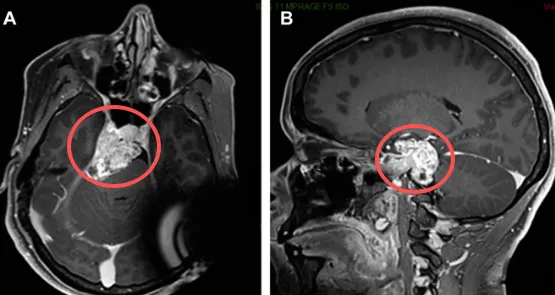

头部受伤,真的会直接导致脑瘤吗?答案通常是否定的。但一次意外,却可能成为发现隐藏的巨大危机的契机。25岁年轻女孩就因头部受伤查出岩斜区肿瘤,剧烈头痛与突发眼睑下垂、视物重影...